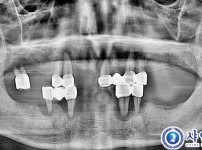

상악 수면임플란트 9개 - 오스템칼슘

구분 임플란트